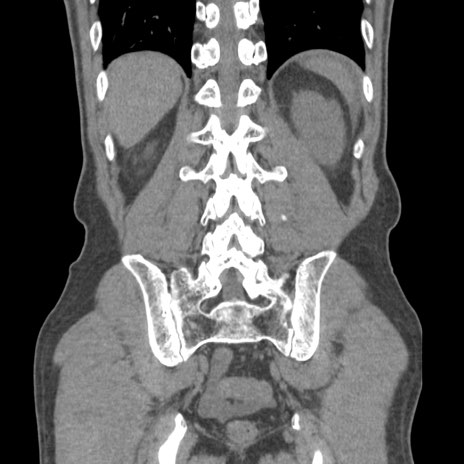

症例56 CT(冠状断像)